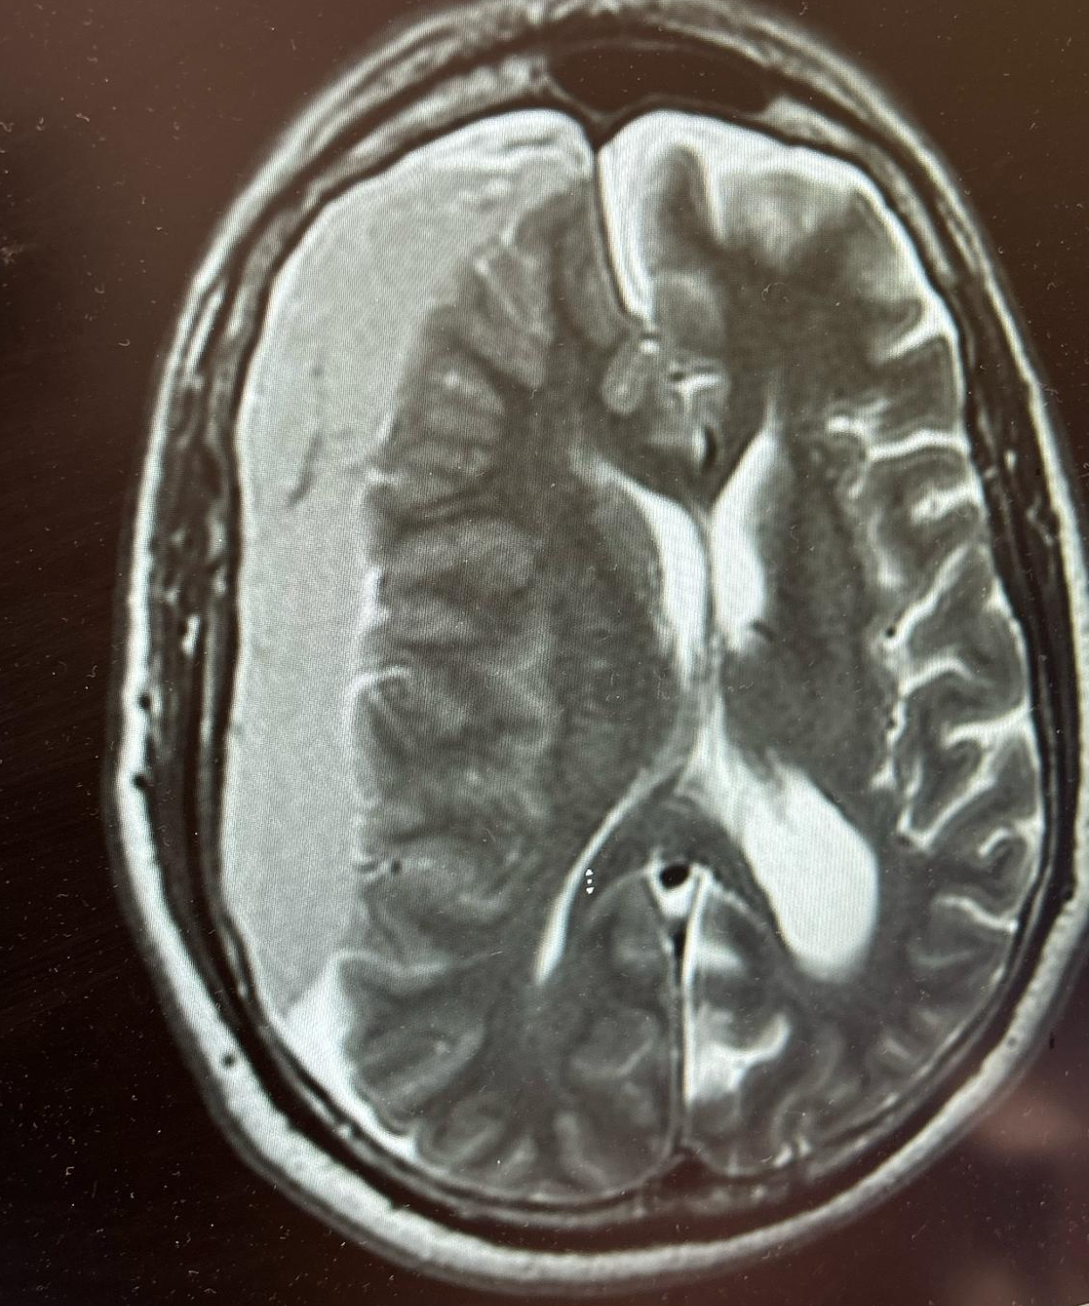

This is a bad brain bleed with midline shift- not good at all

When to Consult Neurosurgery

Realistically you are going to consult neurosurgery for practically every brain bleed... but do it fast if you see:

• Large lobar hemorrhages

• Cerebellar hemorrhages >3 cm

• Significant mass effect (>15 mL volume or >5 mm midline shift)